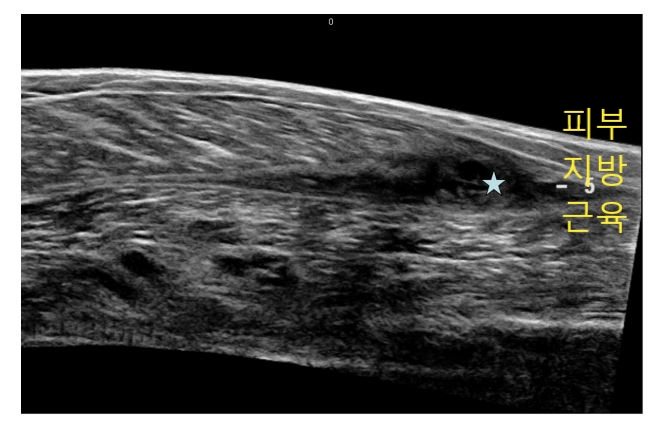

위 이미지의 새까만 곳이

(흰색 화살표)

피가 고인 구역인데요.

다행히도 근육, 뼈에는 이상없이

피하지방층만 손상되었네요.